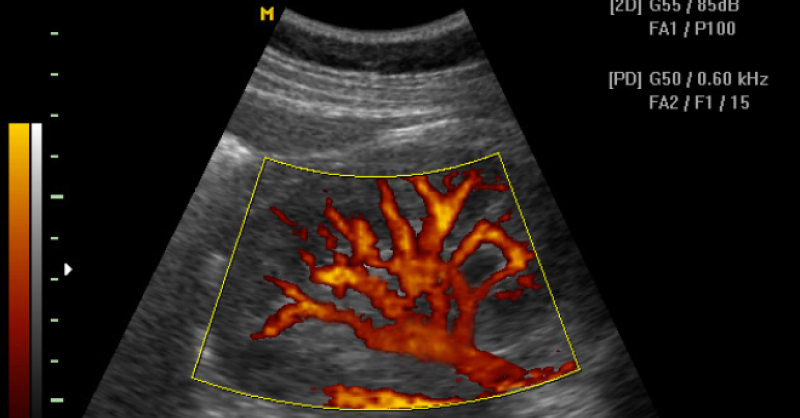

Ecografía doppler

Experimenta la precisión tridimensional de imágenes, desentrañando el flujo sanguíneo y proporcionando una evaluación detallada de la circulación vascular.